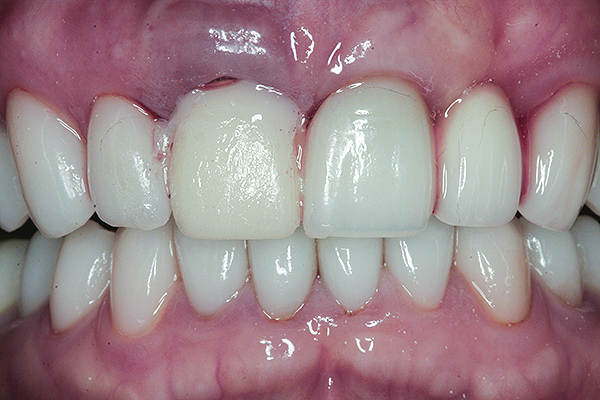

The crown was inserted and secured with a luting composite (Multilink® Automix, Ivoclar Vivadent) (Figure 17); a radiograph confirmed complete removal of excess cement (Figure 18). At the 4-month follow-up appointment, the soft tissues were healed within normal limits, and the patient was pleased with the esthetic outcome of the definitive restoration (Figure 19 and Figure 20).

Fig 19 and Fig 20. Four-month follow-up appointment. The soft tissues had healed within normal limits (Fig 19), and the patient was pleased with the esthetic outcome of the definitive restoration (Fig 20).

Figure 19

Figure 20